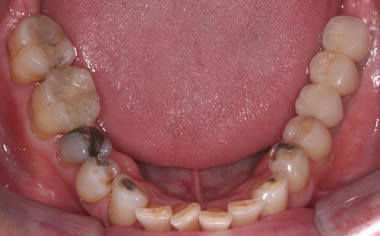

Back teeth replaced by dental implants

Case One (3 images)

Missing lower teeth replaced by three dental implants and crowns.